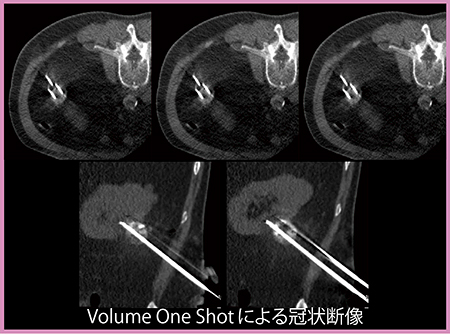

モニタリングのため,凍結中には適宜,320列ADCTのVolume One Shotモードで撮影する(図6)。Volume One Shotでは,1回転0.5秒で160mm幅を撮影できるため,寝台や被検者を動かすことなく広範囲の穿刺状態を確認できる。Volume One Shotでは,撮影後に方向を変えたオブリーク画像も作成することができるため,手技を安全かつ迅速に進めることができる点で大変有用なツールである。今後はさらなるリアルタイム性の向上に期待している。

RCCに対する凍結療法では,ニードルを3本使用することが多い。RCCが腸管に近接している場合はHydrodissection法を併用するが,ニードル3本に加えて造影剤があることで強いアーチファクトが生じ,アキシャル画像に近い3断面透視画像だけでは病変をリアルタイムに正確に把握することが困難となる。そこで当院では,このような症例に対して,オブリーク穿刺により3断面透視画像でニードルを非常に短い範囲だけ描出することで,金属アーチファクトの抑制を図っている(図7)。320列ADCTでは,Volume One Shotを用いることでオブリーク穿刺を比較的容易に行える利点がある。

図6 凍結療法におけるVolume One Shotでのモニタリング

図7 RCC(74歳,男性)に対するオブリーク穿刺